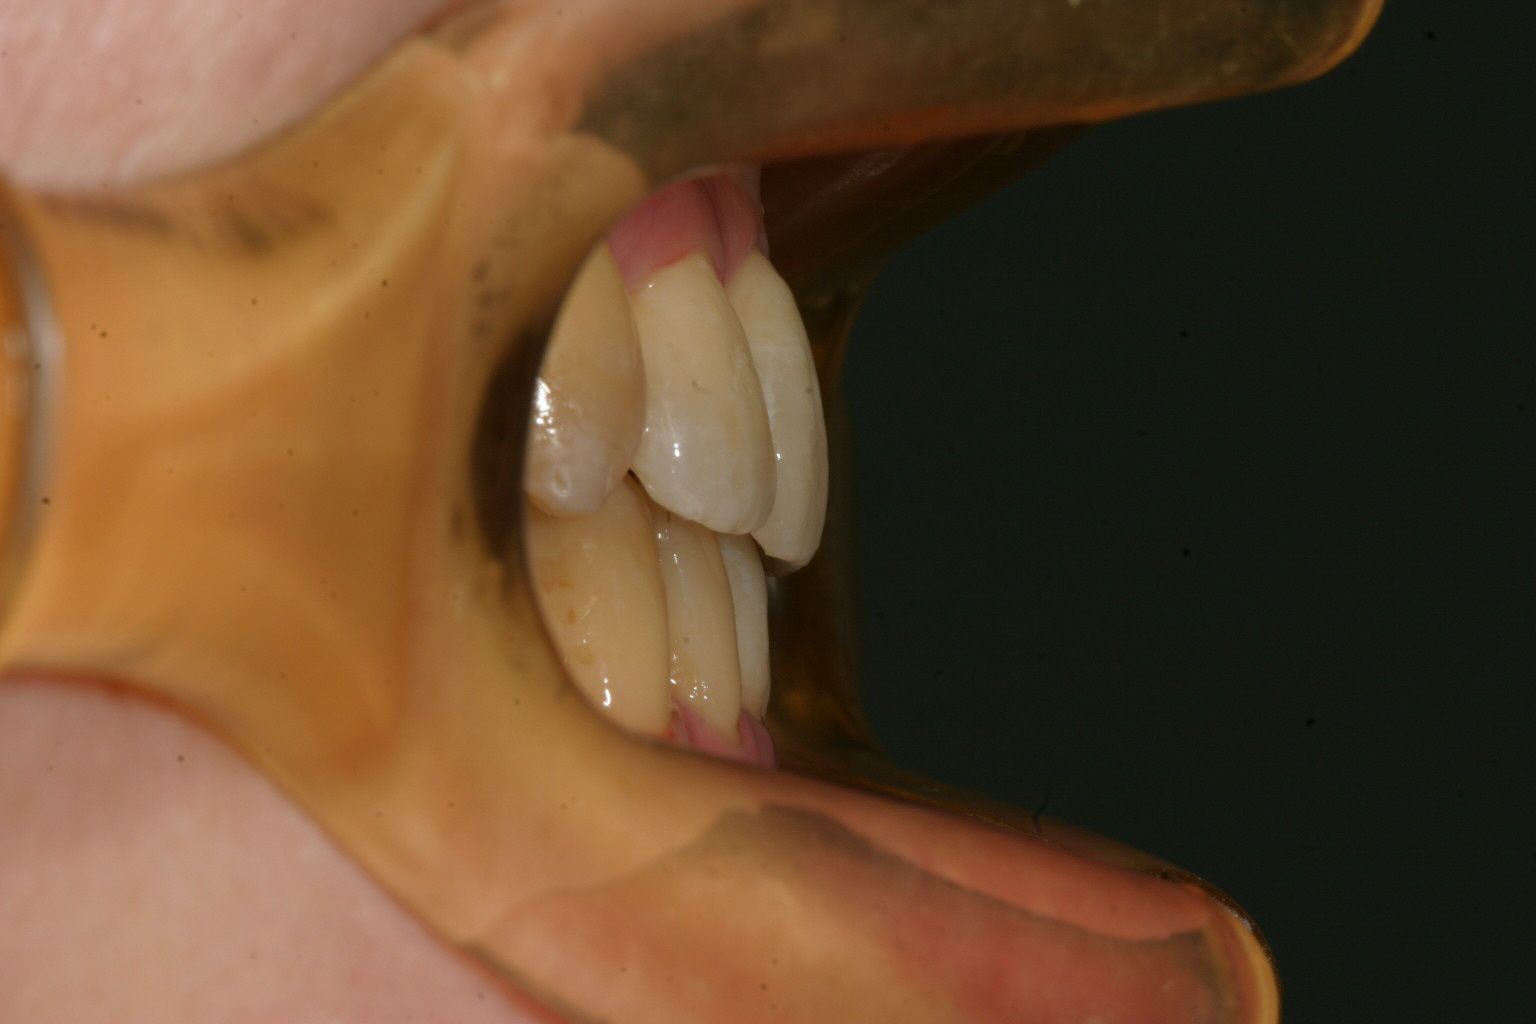

完全に犬歯が飛び出してます。こういう場合は後ろ隣の小臼歯抜いて出来たスペースに糸切り歯を入れます。

左側第二小臼歯が内転してますからこれを抜くことにしましょう。 右側の第二小臼歯も少し内転してますからこれも抜歯する事で左右のバランスを取ります。

犬歯の問題だけでオーバージェット(前歯の前突)はさほど見られません。

小臼歯抜歯した後に綺麗に犬歯が入りました。